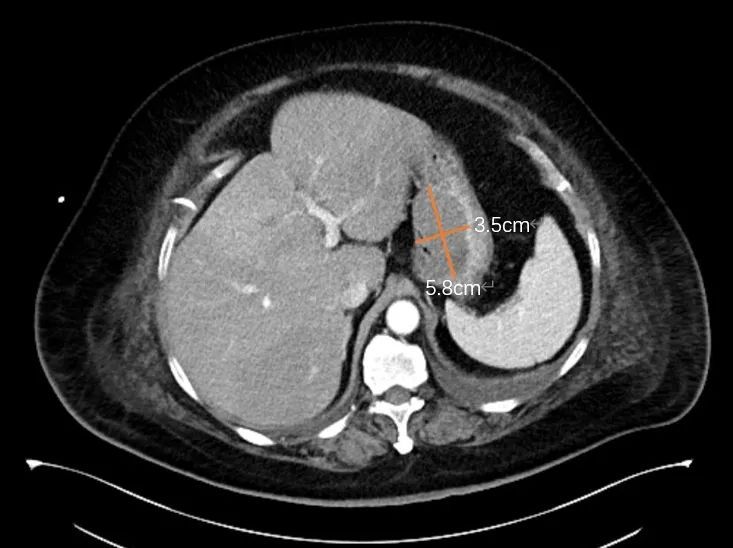

意外发现胃贲门部

有一个5.8cm×3.5cm的肿块

考虑为间质瘤或平滑肌瘤

经过一系列检查,医生分析:王阿姨胃贲门部的肿瘤形态不规则,起源于胃的固有肌层,尽管体积庞大,但主要位于胃腔内。